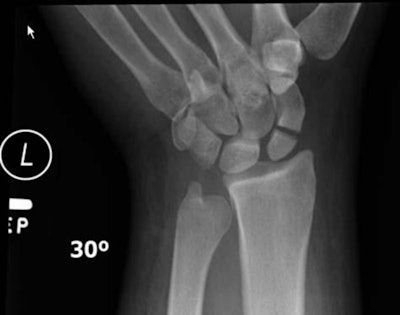

At nearly 32%, the most common type of injury was a wrist fracture (i.e., a distal radius fracture), followed by soft tissue injuries to the head, face, wrist, and ankle in about 26% of the patients.